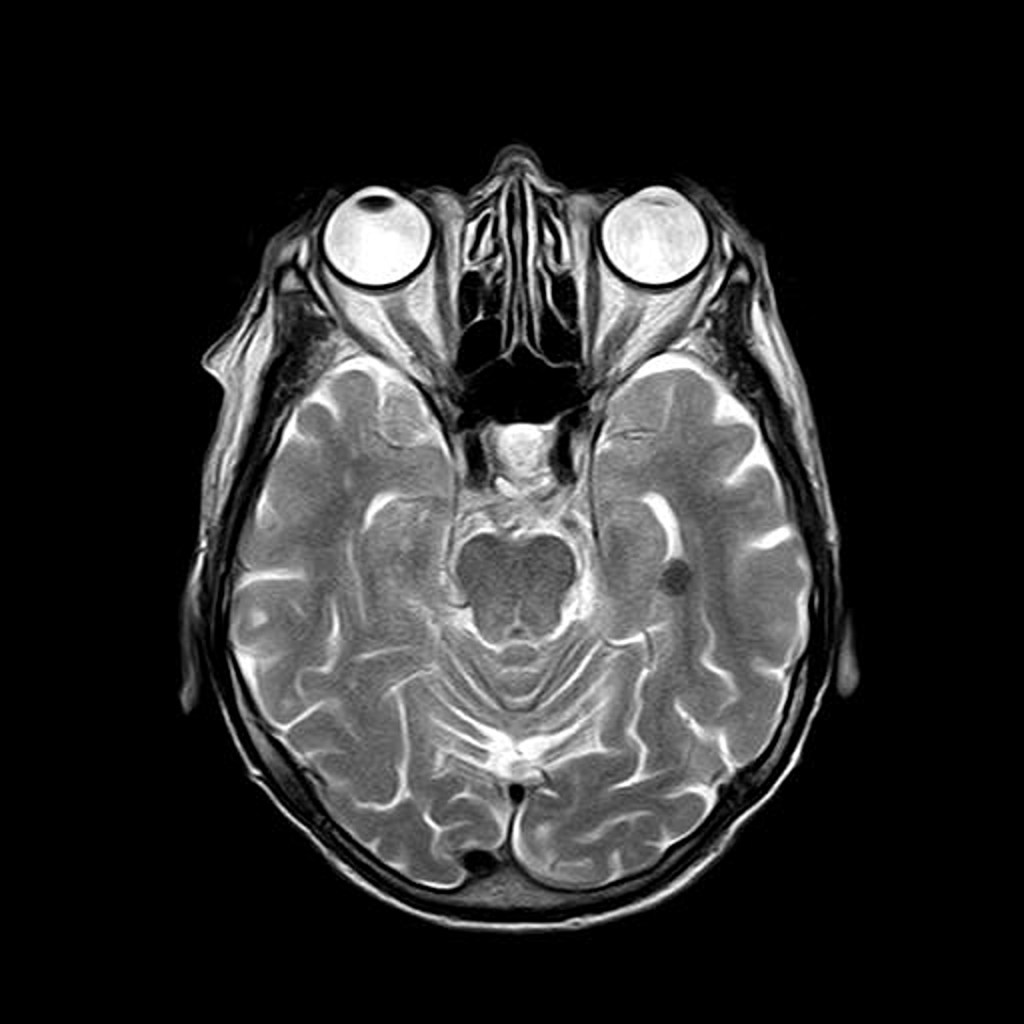

[2] Image retrieved from: https://pixabay.com/illustrations/mri-magnetic-resonance-roentgen-782457/